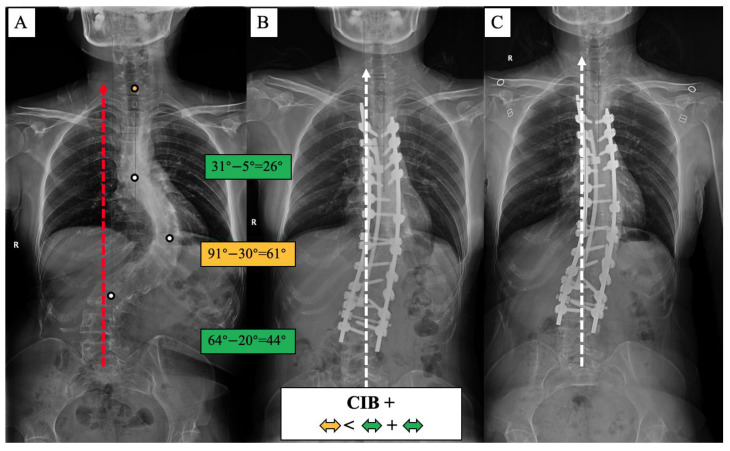

A surgical algorithm was proposed based on the CB classification to avoid postoperation CIB (Figure 3). In addition, a schematic diagram of the correction strategy for each type of patient is shown in Figure 4. For CB+ patients, the correction rate of the main curve (CRMC) should match the compensation curve. For CB− patients, the CRMC should match the compensatory curve. Most of the lumbar motion segments can be retained to provide optimal compensatory ability. However, the postoperative compensatory capacity of CB− patients is not as good as CB+ patients due to the limited mobility of the preserved lumbar motion segments. For CIB− patients, the CRMC should be greater than the compensatory curves. Osteotomy at the concave side of the main thoracolumbar curve is recommended. Multiple-level asymmetrical Ponte osteotomy is a safe and effective technique to improve the flexibility of the spine as well as the correction rate of rigid adult idiopathic scoliosis [ref. 15]. For CIB+ patients, the CRMC should be less than the compensatory curves, and the LIV should be kept even during the surgery. Preserving lumbar mobility is not the primary consideration when making a surgical plan for CIB+ patients. Typical cases are shown in Figure 5, Figure 6, Figure 7 and Figure 8.

CIB+ patients had mechanical instability of the spine, which is similar to the Leaning Tower of Pisa. The postoperative CIB rate, which was 64.28%, had deteriorated at the final follow-up to 71.43%. The results show that CIB+ patients were the least able to compensate. Similar findings have been reported in previous studies of patients with congenital scoliosis and degenerative lumbar scoliosis. In a study of 118 patients with congenital thoracolumbar scoliosis, Liang et al. [ref. 23] reported that patients who lost compensation to the convex side preoperatively had a higher rate of coronal loss postoperatively. Bao et al. [ref. 24] reported that patients with degenerative lumbar scoliosis with type C coronal misalignment, CBD > 3 cm, and C7PL shifted toward the convex side were at greater risk of developing coronal imbalance after posterior osteotomy. Therefore, postoperative CIB needs to be emphasized when consulting with CIB+ patients. The correction of lumbar or lumbar-sacral compensatory curvature is the key to avoiding postoperative CIB in preoperative CIB+ patients. Contrary to CIB− patients, CIB+ patients should have a correction rate of the lumbar or lumbar-sacral compensatory curvature that is greater than that of the main thoracic curvature.